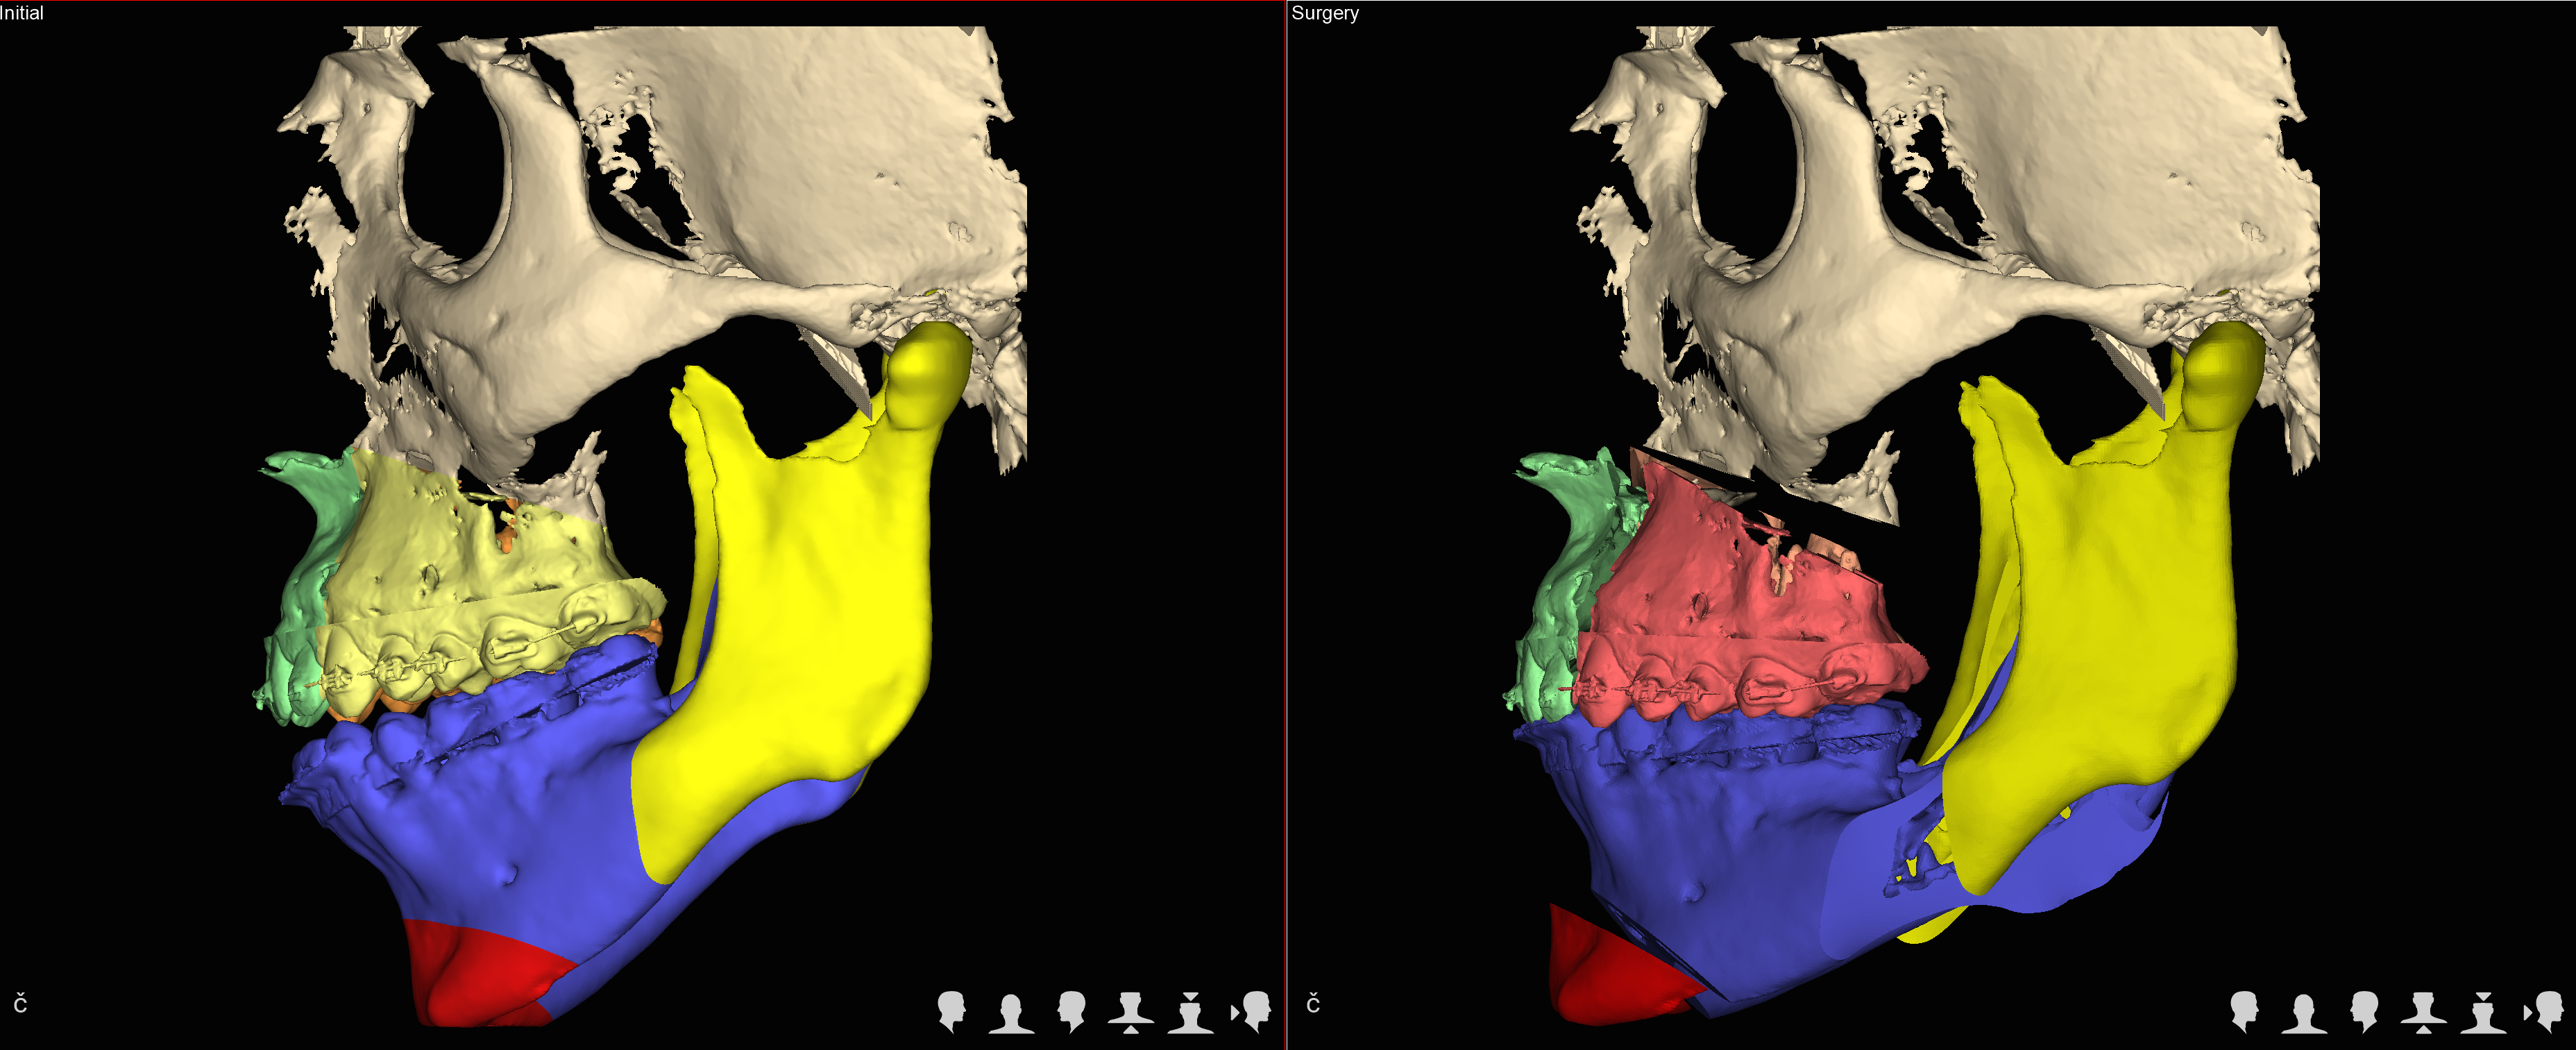

Trójwymiarowe planowanie leczenia wad zgryzu

Nie wyobrażamy sobie planowania operacji wady zgyzu inaczej niż w środowisku 3D.

We współczesnej chirurgii ortognatycznej uzyskanie prawidłowych warunków okluzyjnych czyli prawidłowego zgryzu jest jednym z celów leczenia równie istotnych jak zachowanie prawidłowych stosunków objętościowych w drogach oddechowych czy uzyskanie optymalnej estetyki twarzy.

Jedną z najistotniejszych części leczenia interdyscyplinarnego pacjentów z wadami szkieletowymi jest właściwe zaplanowanie całego procesu leczenia zarówno pod względem przesunięć zębów jak też zmian w układzie kostnym.

Szkielet czaszki twarzowej jest bryłą przestrzenną i rozpatrywanie jego nieprawidłowości w układzie trójwymiarowym pozwala na prawidłowe ich zdiagnozowanie a tym samym na optymalne zaplanowanie przesunięć kostnych, uzyskanie właściwych proporcji twarzy.

W naszym Centrum wykorzystujemy koncepceję FAB (FaceAirwayBite) opracowaną przez Williama Arnetta – światowej sławy chirurga zajmującego się leczeniem wad zgryzu.

Następnie rekomendujemy lub wdrażamy postępowanie ortodontyczne. Po jego zakończeniu przystępujemy ponownie do analiz wszystkich parametrów w obrębie twarzy i przygotowujemy plan leczenia chirurgicznego obejmjący przesunięcia kostne z zakresie układu szkieletowego z uwględnieniem koncepcji FAB.

Docelowo efektem jest wydruk szablonów chirurgicznych na drukarce 3D.

W trakcie planowania powstają rownież symulacje efektów leczenia (symulacje a więc nie gwarantowany efekt), które są przedstawiane pacjentowi przed wykonaniem zabiegu.